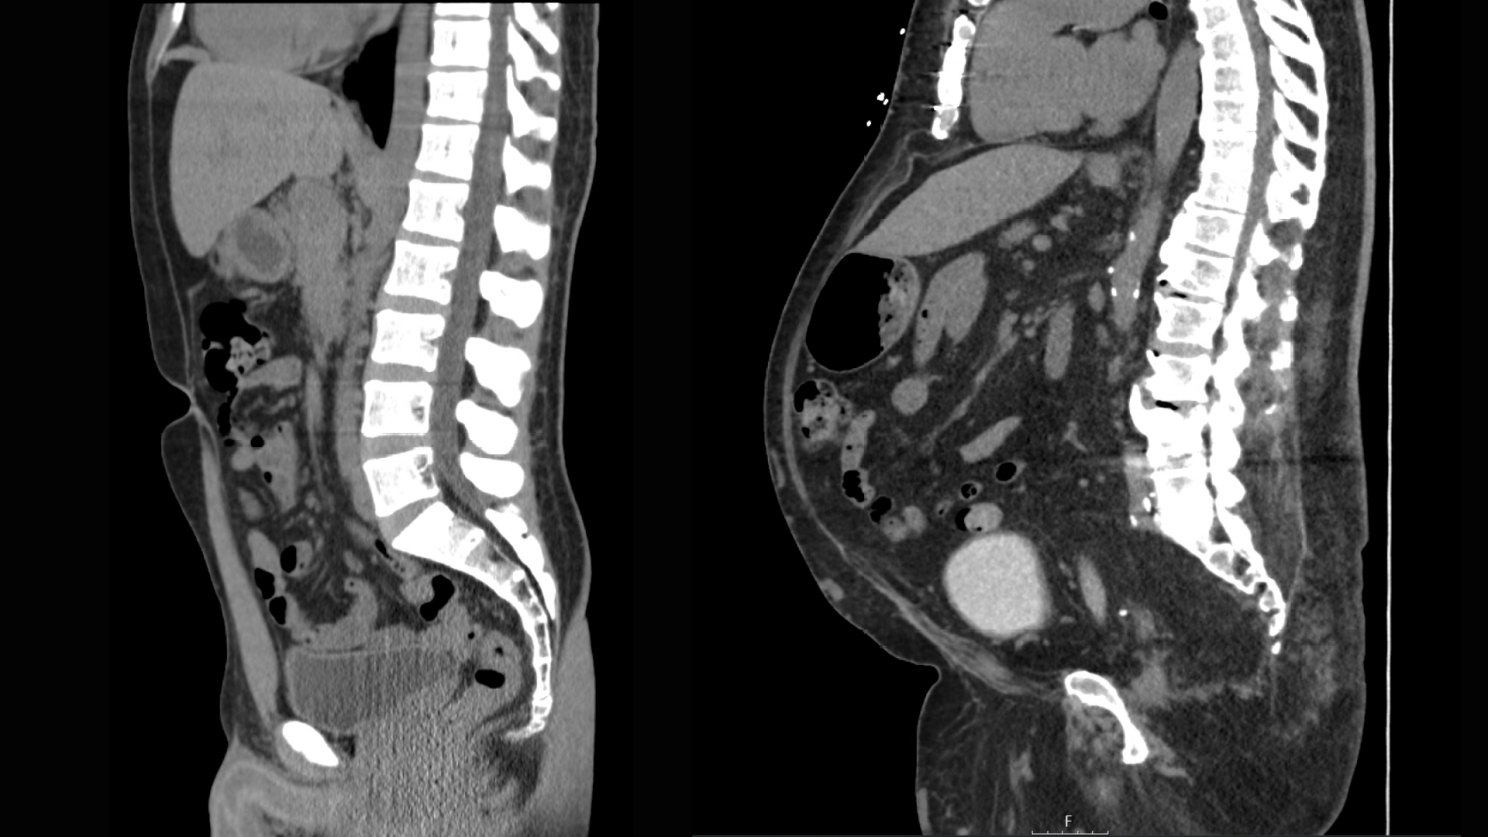

Advanced Imaging: MRI and CT scans remain the gold standard for precise visceral fat measurement. That said, they're typically reserved for research or specific clinical situations.